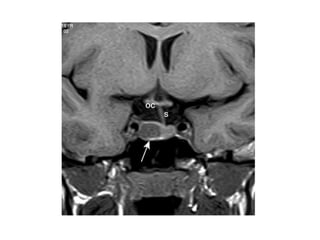

Síndrome de la silla turca vacía

• Primario

– Falla el diafragma de la silla (hernia de la aracnoides y del

LCR) ↑ tamaño de la silla y comprime la hipófisis.

• (Mujeres multíparas obesas – campo visual)

– Anomalías endocrinas

• Hiperprolactinemia (interrupción del efecto inhibidor

hipotalámico).

– La ↓ parénquima funcional puede causar

hipopituitarismo.

• Secundario

– Masa que ↑ tamaño de la silla (Qx o necrosis espontánea).

– El hipopituitarismo puede ser causado por el tto o por un

infarto espontáneo.

Síndrome de la silla turca vacía, vista macroscópica

En esta imagen de autopsia se ha extraído el cerebro y se ve la base del cráneo, con la

silla turca en el centro. Tan sólo hay un resto aplanado de hipófisis en la base de la

silla turca.